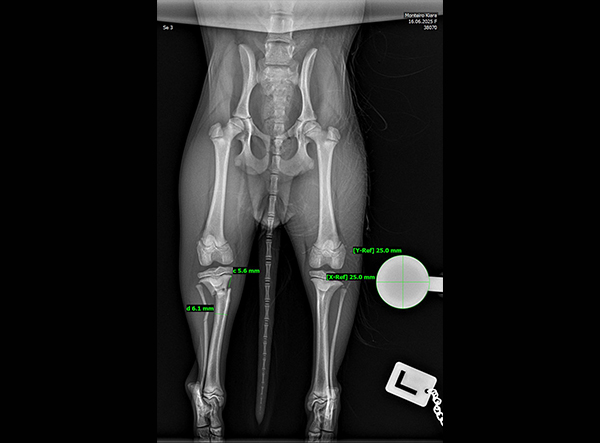

The patient, an 18-week-old female Yorkshire Terrier, was referred for surgery on October 21, 2025. The dog had sustained a fall from the owner’s arms, resulting in a fracture of the proximal tibial metaphysis just below the growth plate, along with a fibular fracture. Given the patient’s very small size and young age, precise anatomical fixation and minimal disruption of the growth zone were essential.

An open reduction and internal fixation (ORIF) was performed via a medial approach to the proximal tibia.Implant Used: 1.5 mm LeiLOX TPLO Swing Titanium Plate

The surgery was completed without complications. Postoperative radiographs confirmed anatomical alignment and stable fixation. With careful rehabilitation, the young Yorkshire Terrier is expected to regain full function and resume normal activity pain-free.